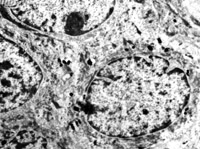

5-2-2 伤后第1天,毛细血管内皮细胞核固缩,管腔内血液凝聚和瘀滞  TEM×6000